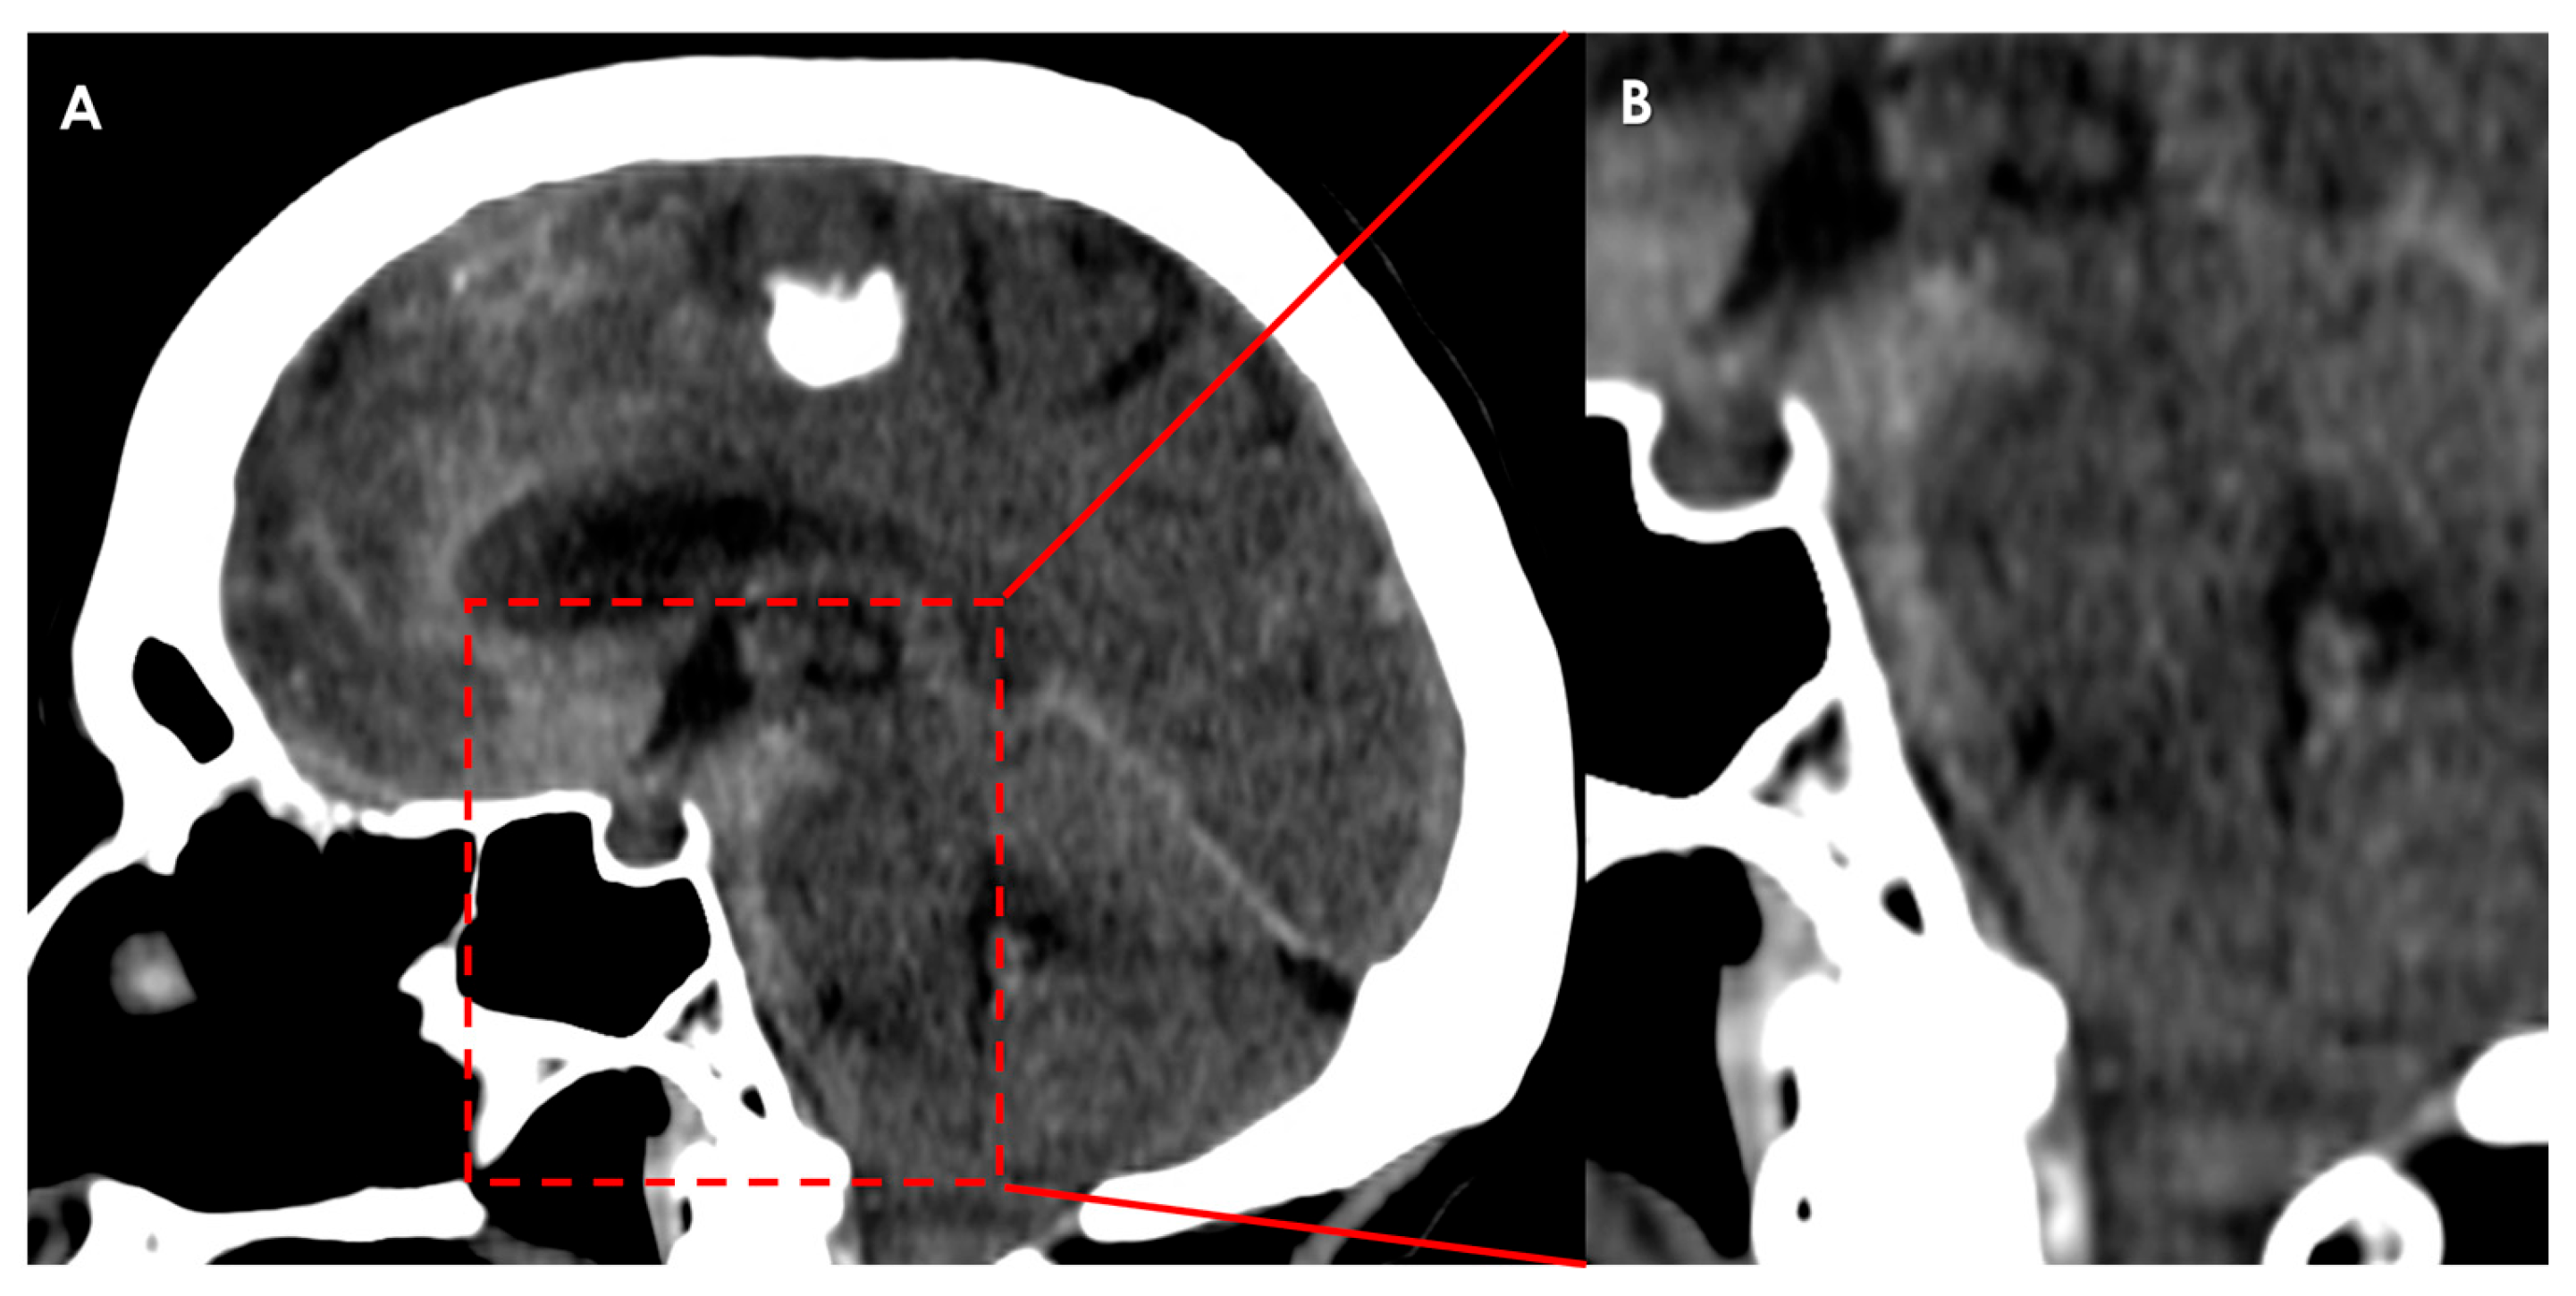

4.2. Subarachnoid Hemorrhage